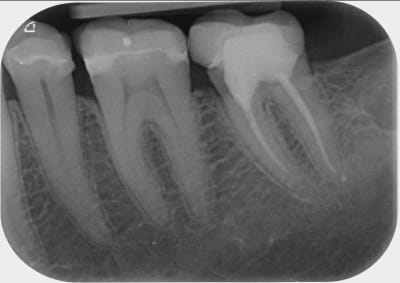

A toutes fins utiles, pour les nouveaux lecteurs, je reposte mes radios.

en ajoutant la 42 également.

J'espère ne pas avoir de problème neuropathique...car j'ai également maintenant une sensibilité sur la 42...cela me l'avait déjà fait..il y a 1 an..et mon patron n'avait rien trouvé.

Je mets un très gros billet sur une interférence / ou surguidage 6-7

Et retraitement à réaliser sur la 7 car incomplet . Je ne critique pas, ça peut arriver que ça soit très difficile d’accéder jusqu’à l’apex.

+1 .moi j y mets un billet violet :-)

avec en plus un encombrement incisif ( sur-contact retropulsif )